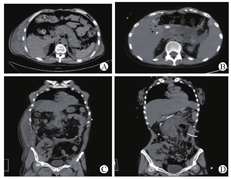

12例受者均在出现上腹部疼痛后72 h内确诊为急性胰腺炎(4例为急性重症胰腺炎),其中4例于术后7 d内发病,通过纠正低血容量休克及水电解质酸碱平衡紊乱,并给予胃肠外营养支持等非手术治疗后痊愈2例,2例行胰腺周围间隙穿刺引流术治愈;8例于术后1年后发生急性胰腺炎,其中3例经非手术治疗痊愈,5例接受了手术治疗;5例手术治疗的受者中,1例接受腹腔镜胆囊切除术,1例经内镜逆行胰胆管造影(ERCP)下胆道取石治疗,2例接受胰腺周围间隙穿刺引流术,1例接受胰腺周围坏死组织清创引流术;1例因发生多器官功能衰竭而死亡(表2,图1)。